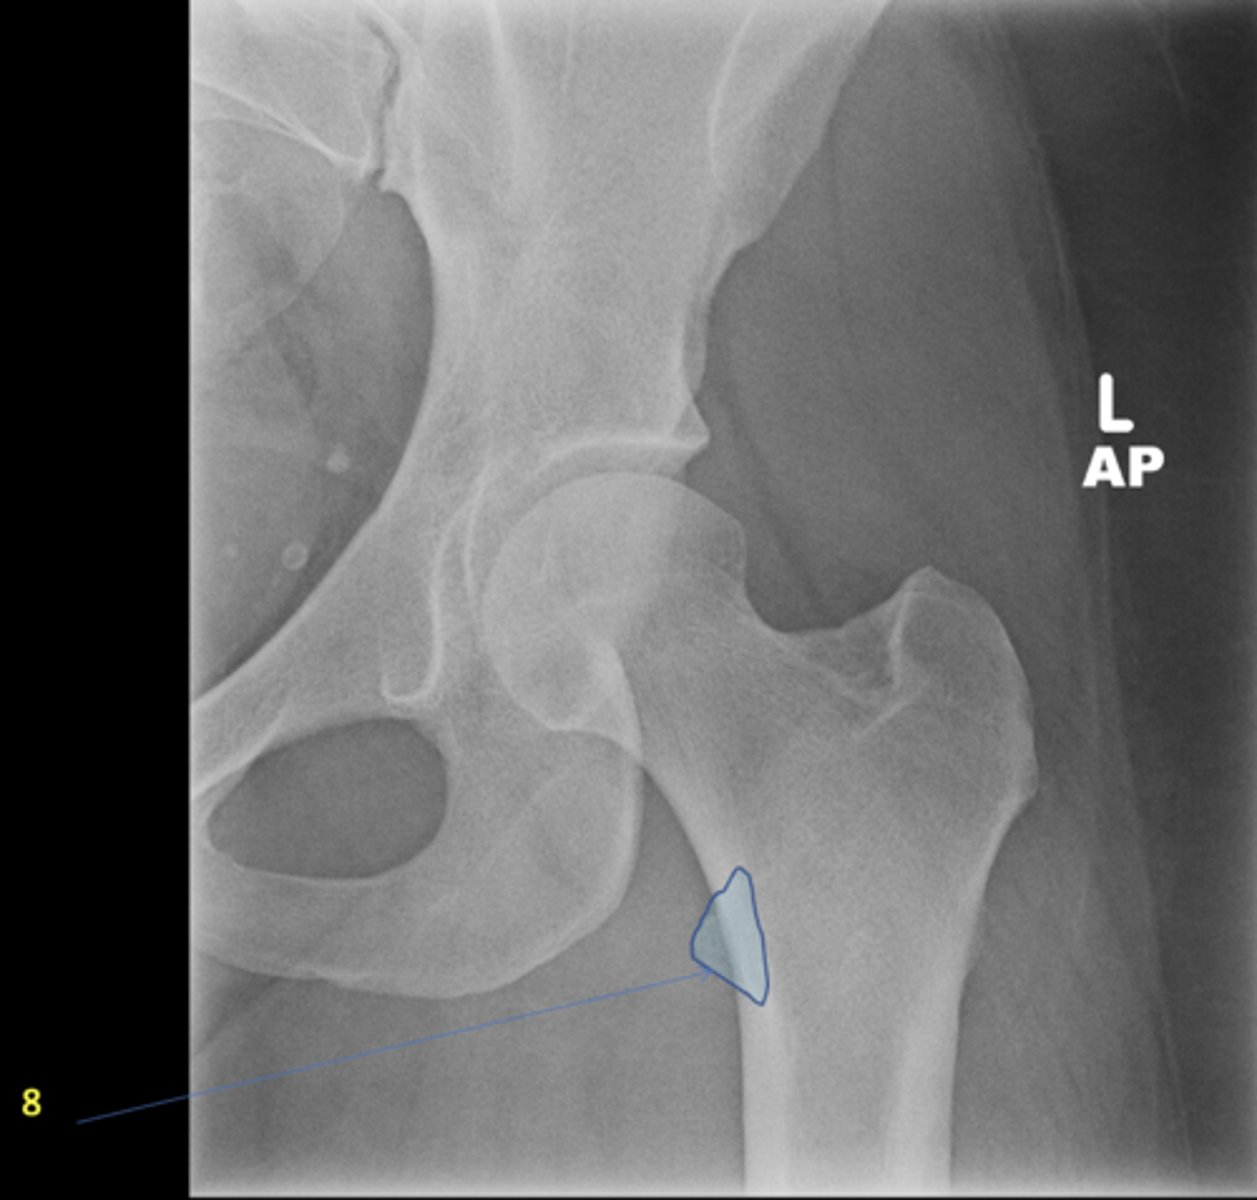

8

New cards

Left ischial spine

ID 8

<p>ID 8</p>